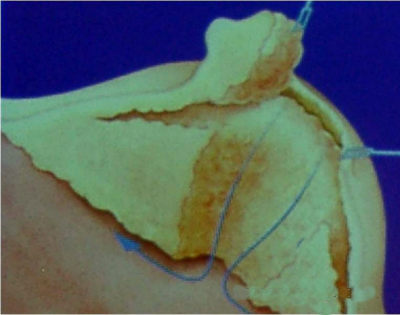

בניתוח זה, בנוסף לכריתה המבוצעת ב-Radical mastectomy, מבצעים בנוסף פתיחת בית החזה דרך סחוסי הצלעות ומבצעים כריתה של בלוטות לאורך ה-Internal Mammary (איור 26.12). ניתוח זה אינו מקובל, מכיוון שניתן להקרין את הבלוטות האלה, ולקבל תוצאות דומות מבחינת ההיוותרות בחיים.